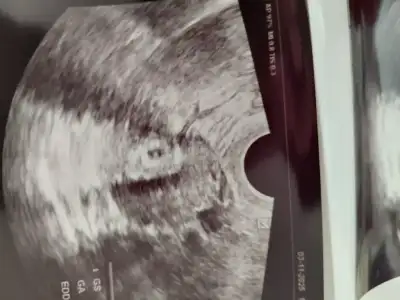

Kese ve yok kesesi görünüyor dedi hatta bebeğimize içerde gibi bir şey dedi ama ben heyecandan beynim durduğu için anlamadım resimde belli gibi sanki

tek yumurta ikizi gibi duruyor ama bir dahaki kontrolde net bişey söylerim dedi doktor merakla bekliyoruz zamanda geçmiyor bekleyince :) inşallah sağlıkla ikiside gelişir büyür aralarındaki fark normaldir inşallah

İki kesemi var tek kesemi anlayamadımı demekki kücükler baya🥰. Bir daha ne zaman gidiceksiniz. İkiz gebelikler beni cok heyecanlandırır